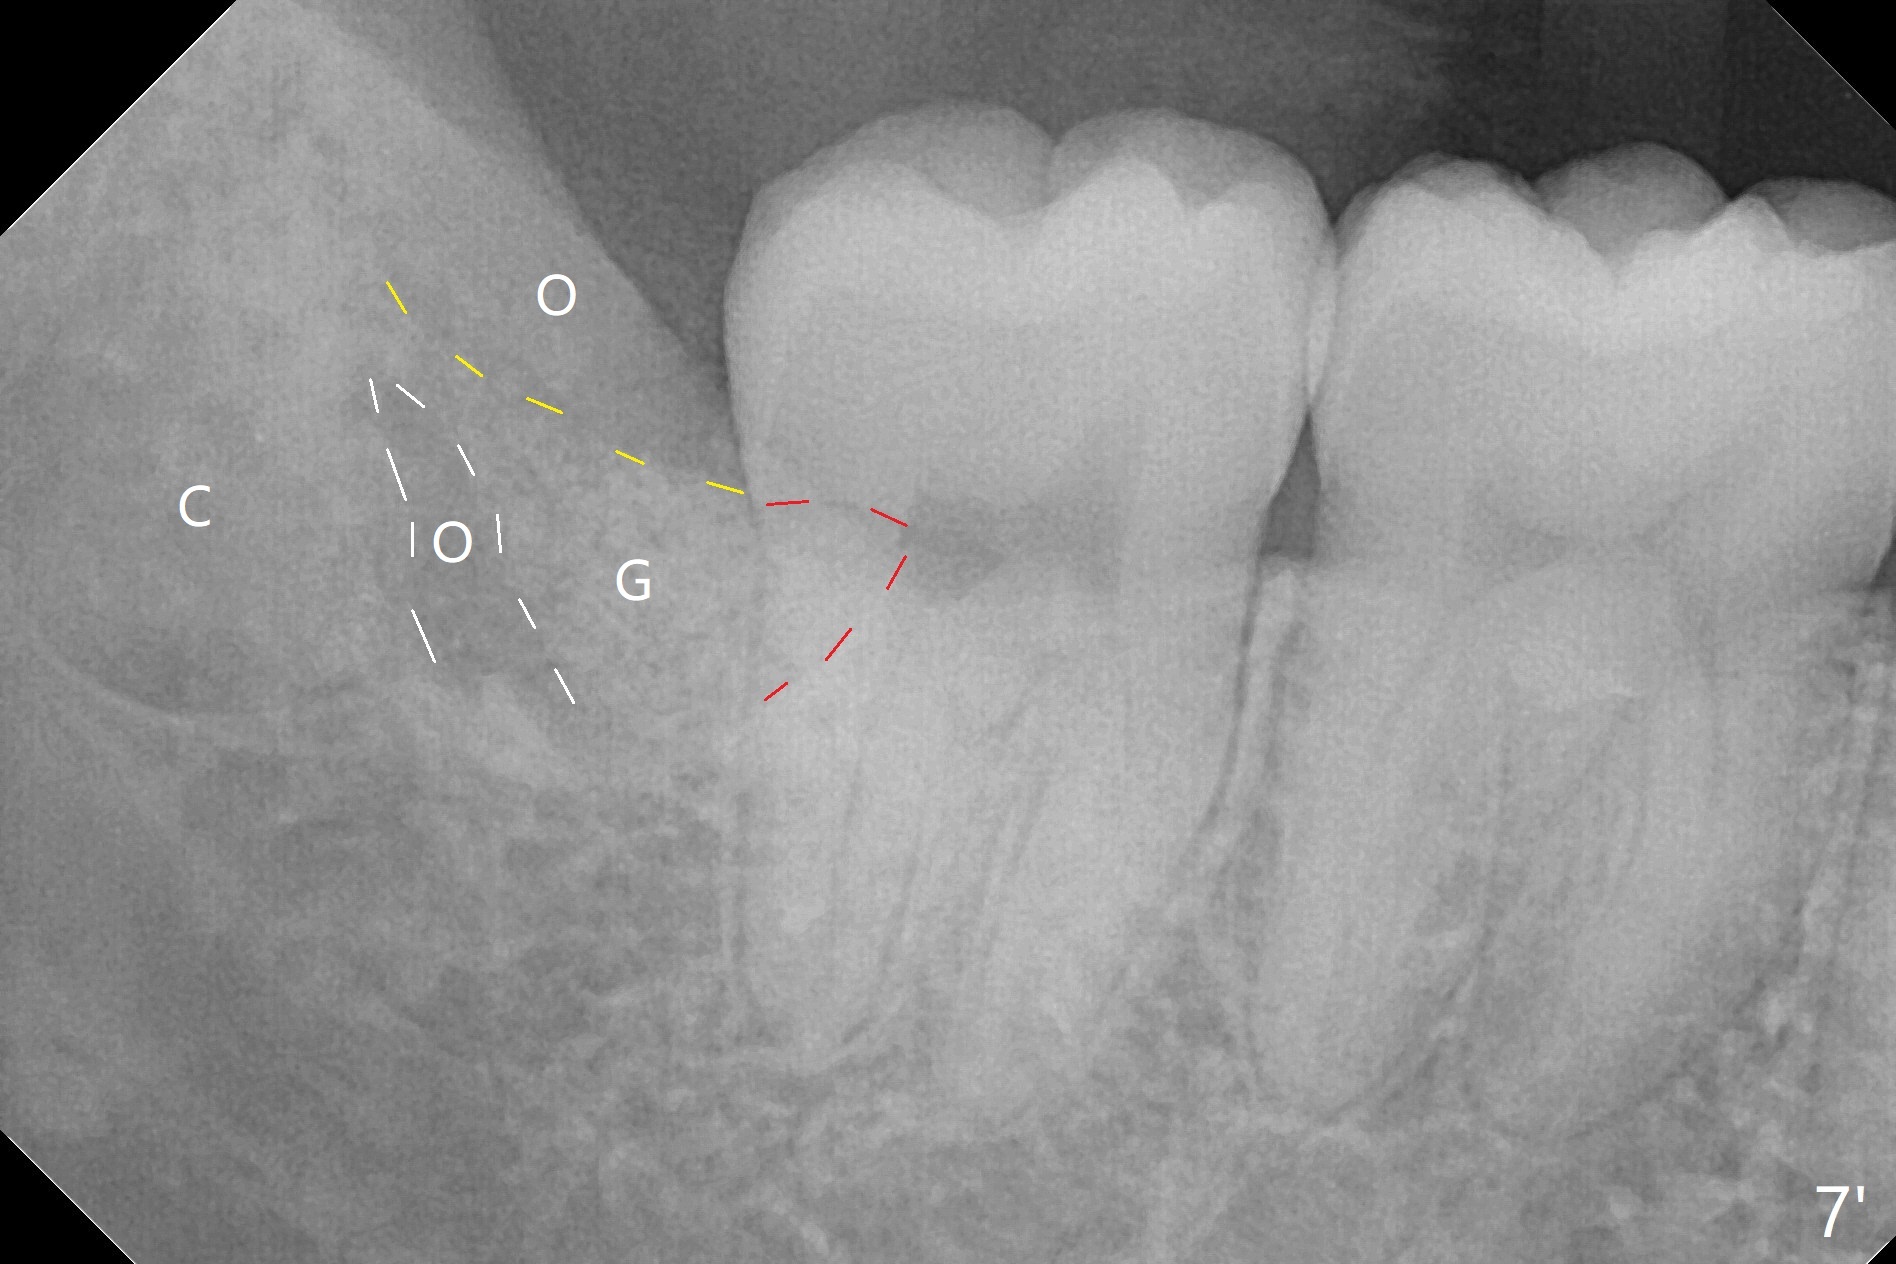

In fact the tooth #32 is extracted first; the defect involves the distobuccal aspect of the tooth #31 (Fig.4 *). An intraop PA is taken after extraction to confirm whether a broken surgical fissure bur tip retains or not; the distal lamina dura of #31 is low (Fig.5 *). It is expected to increase after cocktail bone graft (Fig.5' arrow). As planned, the bone cement (Fig.6 C) and allograft (G) are placed in the distal and mesial portions of the socket; between them is Osteogen Plug (O). Another piece of Osteogen Plug (as collagen membrane for bone graft) is placed on the top of the socket before suturing with 4-0 Plain Gut (Fig.7,7' O). Also note the bone graft being placed distobuccal (CT study) to #31 (Fig.7' red dashed line) to reduce possibility of future periodontitis. The patient returns 15 days postop with chief complaint of mild pain since extraction, although the wound looks normal. The transverse cortex connecting to the lamina dura (Fig.5 *) is obliterated when allograft is placed (Fig.7 G). The part of the graft remains in place 1 month postop (Fig.9) in spite of wound dehiscence (Fig.8). The bone graft loss is indicated by the fact of the reappearance of the transverse cortex (Fig.9). In the same appointment, the tooth #17 (Fig.10) is being extracted (Fig.11), leaving a defect mesiobuccal (Fig.12 *) to distal (curette). Part of Osteogen plug (Fig.13 O) is stretched to cover the mesially placed allograft (Fig.14 G). One quarter of Collagen plug is placed over the Osteogen plug (Fig.13 O) before 4-0 PGA suturing. There is bone regeneration 1 year postop (Fig.15,16).